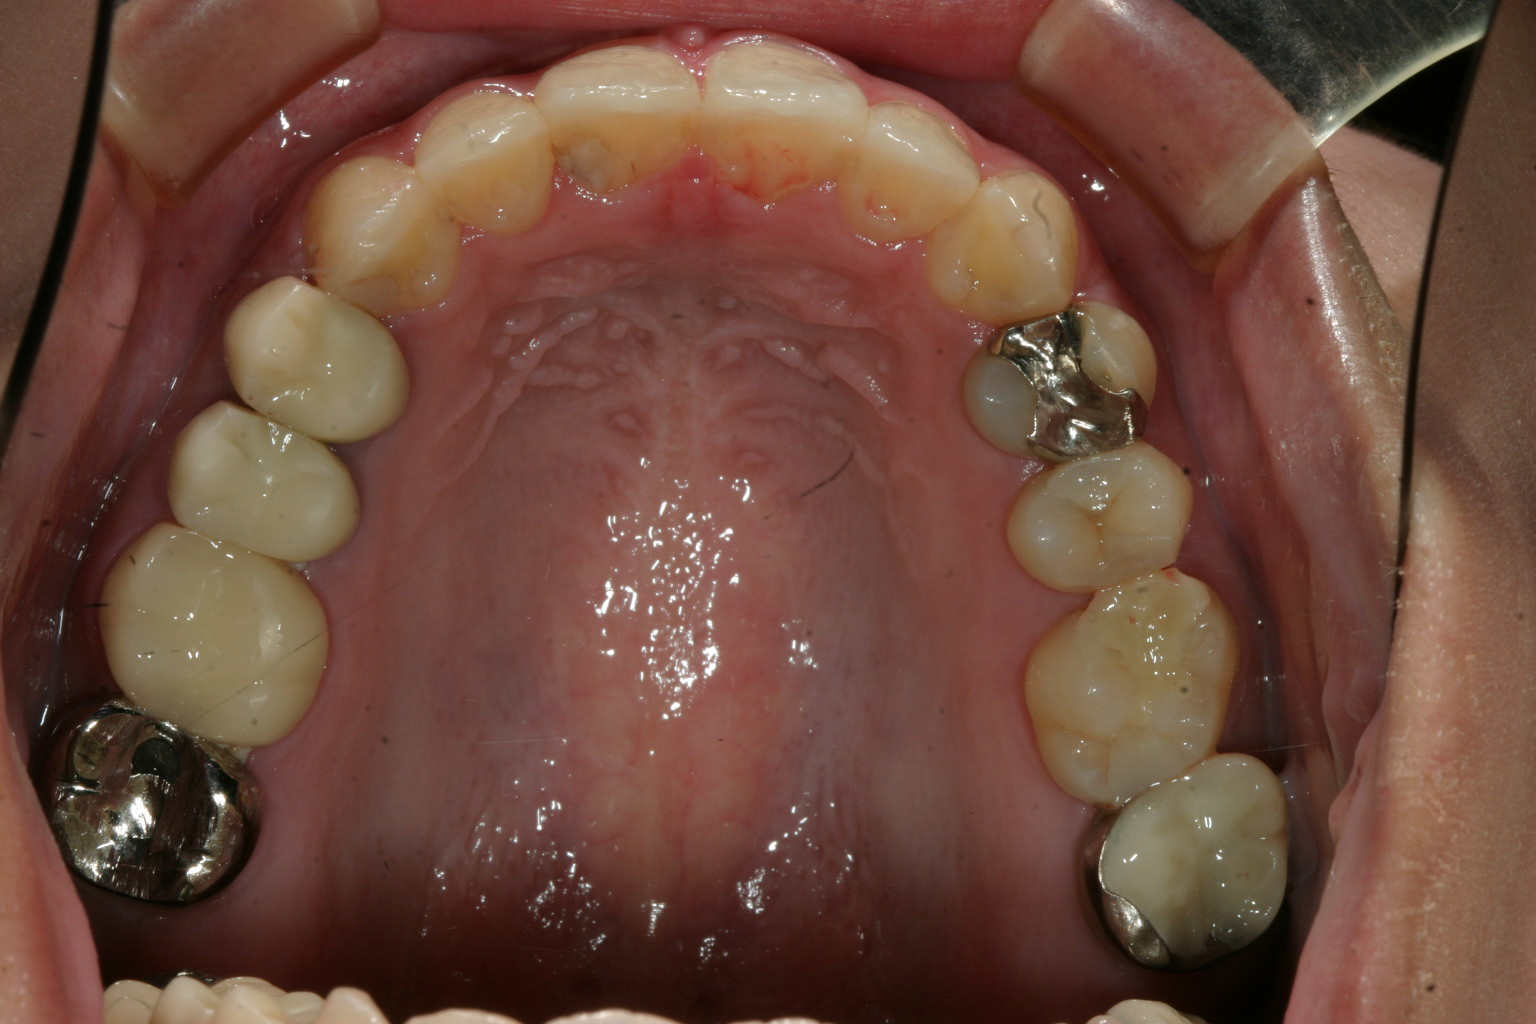

前歯がねじれています、これを翼状捻転って言います。

前歯がねじれている分少し出っ歯に見えます。